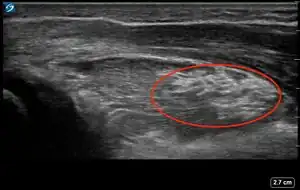

| 4 | Pronator quadratus hematoma[17][14][18] | ![]() Ultrasound view of pronator quadratus hematoma (PQH) sign (area inside red oval) which is identified by an increased thickness and brighter appearance of the pronator quadratus muscle compared to the pronator quadratus muscle of the unaffected forearm. |